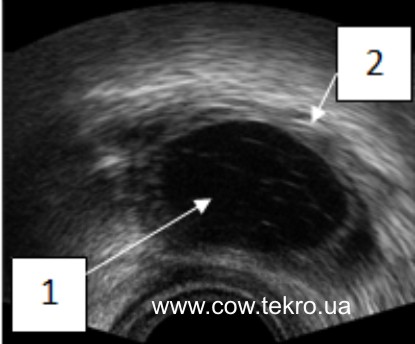

За ультразвукового дослідження фолікулярна кіста має вигляд ехонегативних порожнин (має чорний колір) з ехопозитивною капсулою (світло-сірий колір) (рис. 8).

Рисунок 8 – Ехограма фолікулярної кісти яєчника корови: 1 – ехонегативне порожнина; 2 – ехопозитивна капсула